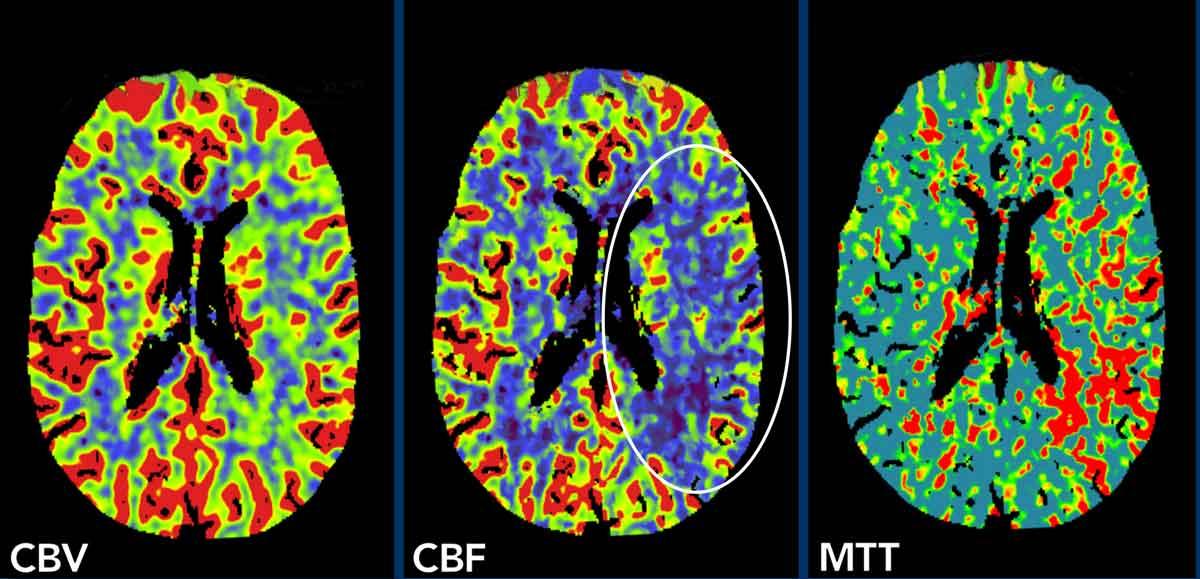

Những hình ảnh này của một bệnh nhân nhập viện với tình trạng khởi phát đột ngột khó nói lưu loát.

Khám thực thể phát hiện đồng tử hai mắt không đều nhau và có dấu hiệu bán manh bên phải.

Bệnh nhân được chuyển đến đơn vị đột quỵ.

Chụp CT không tiêm thuốc cản quang cho kết quả bình thường, loại trừ xuất huyết.

Hình ảnh

Các hình ảnh tưới máu cho thấy thể tích máu não (CBV) và lưu lượng máu não (CBF) giảm nhẹ trong vùng phân bố của động mạch não giữa bên trái (vòng tròn) và thời gian vận chuyển trung bình (MTT) tăng.

Bệnh nhân này bị tắc nghẽn M3, có thể thấy khi chúng tôi cuộn qua các hình ảnh (không hiển thị)

Tuy nhiên, tắc nghẽn M3 chỉ có thể giải thích một phần nhỏ các phát hiện trên hình ảnh tưới máu.

Trong những trường hợp đó, bạn luôn phải nghiên cứu động mạch cảnh trong.

Hình ảnh bên phải cho thấy hình ảnh CTA điển hình của bóc tách động mạch cảnh với hình ngọn lửa xuất hiện vài centimet phía trên chỗ phân đôi (đầu mũi tên).

Two weeks later and MRI was performed.

Khối máu tụ trong thành của bóc tách được hiển thị rõ ràng (mũi tên).

Vào thời điểm đó, hội chứng Horner bên trái cũng được ghi nhận và điều này có thể được giải thích bởi sự chèn ép của khối máu tụ trong thành động mạch cảnh trong lên hệ thống hậu hạch (tế bào thần kinh bậc ba) đi trong lớp áo ngoài của động mạch cảnh trong và động mạch cảnh ngoài đến xoang hang.

Ở những bệnh nhân này, hội chứng Horner có thể hồi phục khi khối máu tụ thu nhỏ lại, như đã xảy ra ở bệnh nhân này sau khi điều trị bằng thuốc kháng kết tập tiểu cầu.